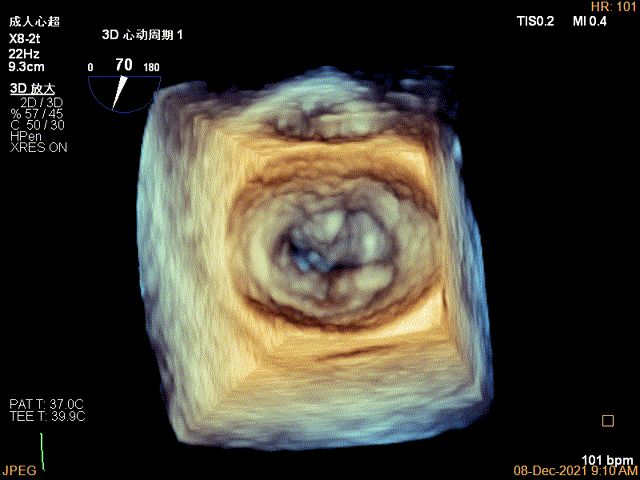

3D视图菲薄的卵圆窝,穿刺点位近似于3点位

3D-VIEW验证结果

3D-Color-view验证残余分流位于外侧